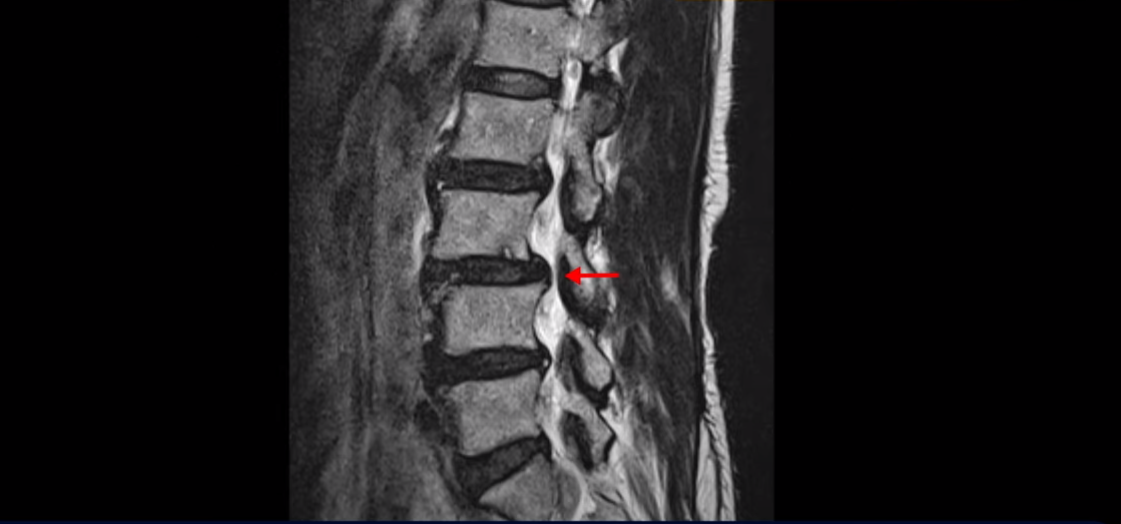

이분 허리를 보면 여러 마디의 퇴행성 디스크와 협착이 있습니다.

2번 3번과 3번 4번은 신경다발이 지나가는 척추관도 좁아져 있습니다.

또 3번 4번에는 척추뼈가 밀려나간 전방전위증도 있습니다.

이분은 정형외과 병원에서 3마디 디스크 파열이라고 수술 권유를 받았는데 저희는 디스크 파열은 잘못된 진단이라고 봅니다. 여러 마디 보이는 디스크 문제는 파열이 아닌 퇴행성디스크들이고 아픈 원인은 전방전위와 협착증 증상입니다. 전방전위와 협착증이긴 하지만 아주 심한 게 아니고 발병한지도 얼마 되지 않아서 근육재활치료를 하면 2주 정도면 빨리 호전될 수 있는 상태였습니다. 왜 이런 환자가 치료하기 훨씬 쉬운 건지, 치료는 어떻게 하는 건지 지금부터 설명 드립니다.

그럼 왜 2주 전에 갑자기 아프게 된 걸까요? 바로 근육에 문제가 생겼기 때문입니다. 60세 넘어서 근육이 줄어들고 약해진 상태에서 무리한 일이나 운동 등으로 근육에 문제가 생기면 허리를 잘 지지하지 못하니까 신경이 자극되고 눌리는 증상이 생기는 겁니다. 신경 구멍이 좁아져 있으니까 근육에 문제가 생기면 신경 자극 증상이 더 쉽게 나타나는 겁니다. 이분은 치료시작 2주 전에 20키로 나가는 손녀를 업어주다가 허리 근육에 문제가 생겼습니다. 신경 구멍이 좁아져 있는데 근육에 문제가 생겨서 허리를 잘 지지하지 못하니까 신경이 자극되기 시작합니다.